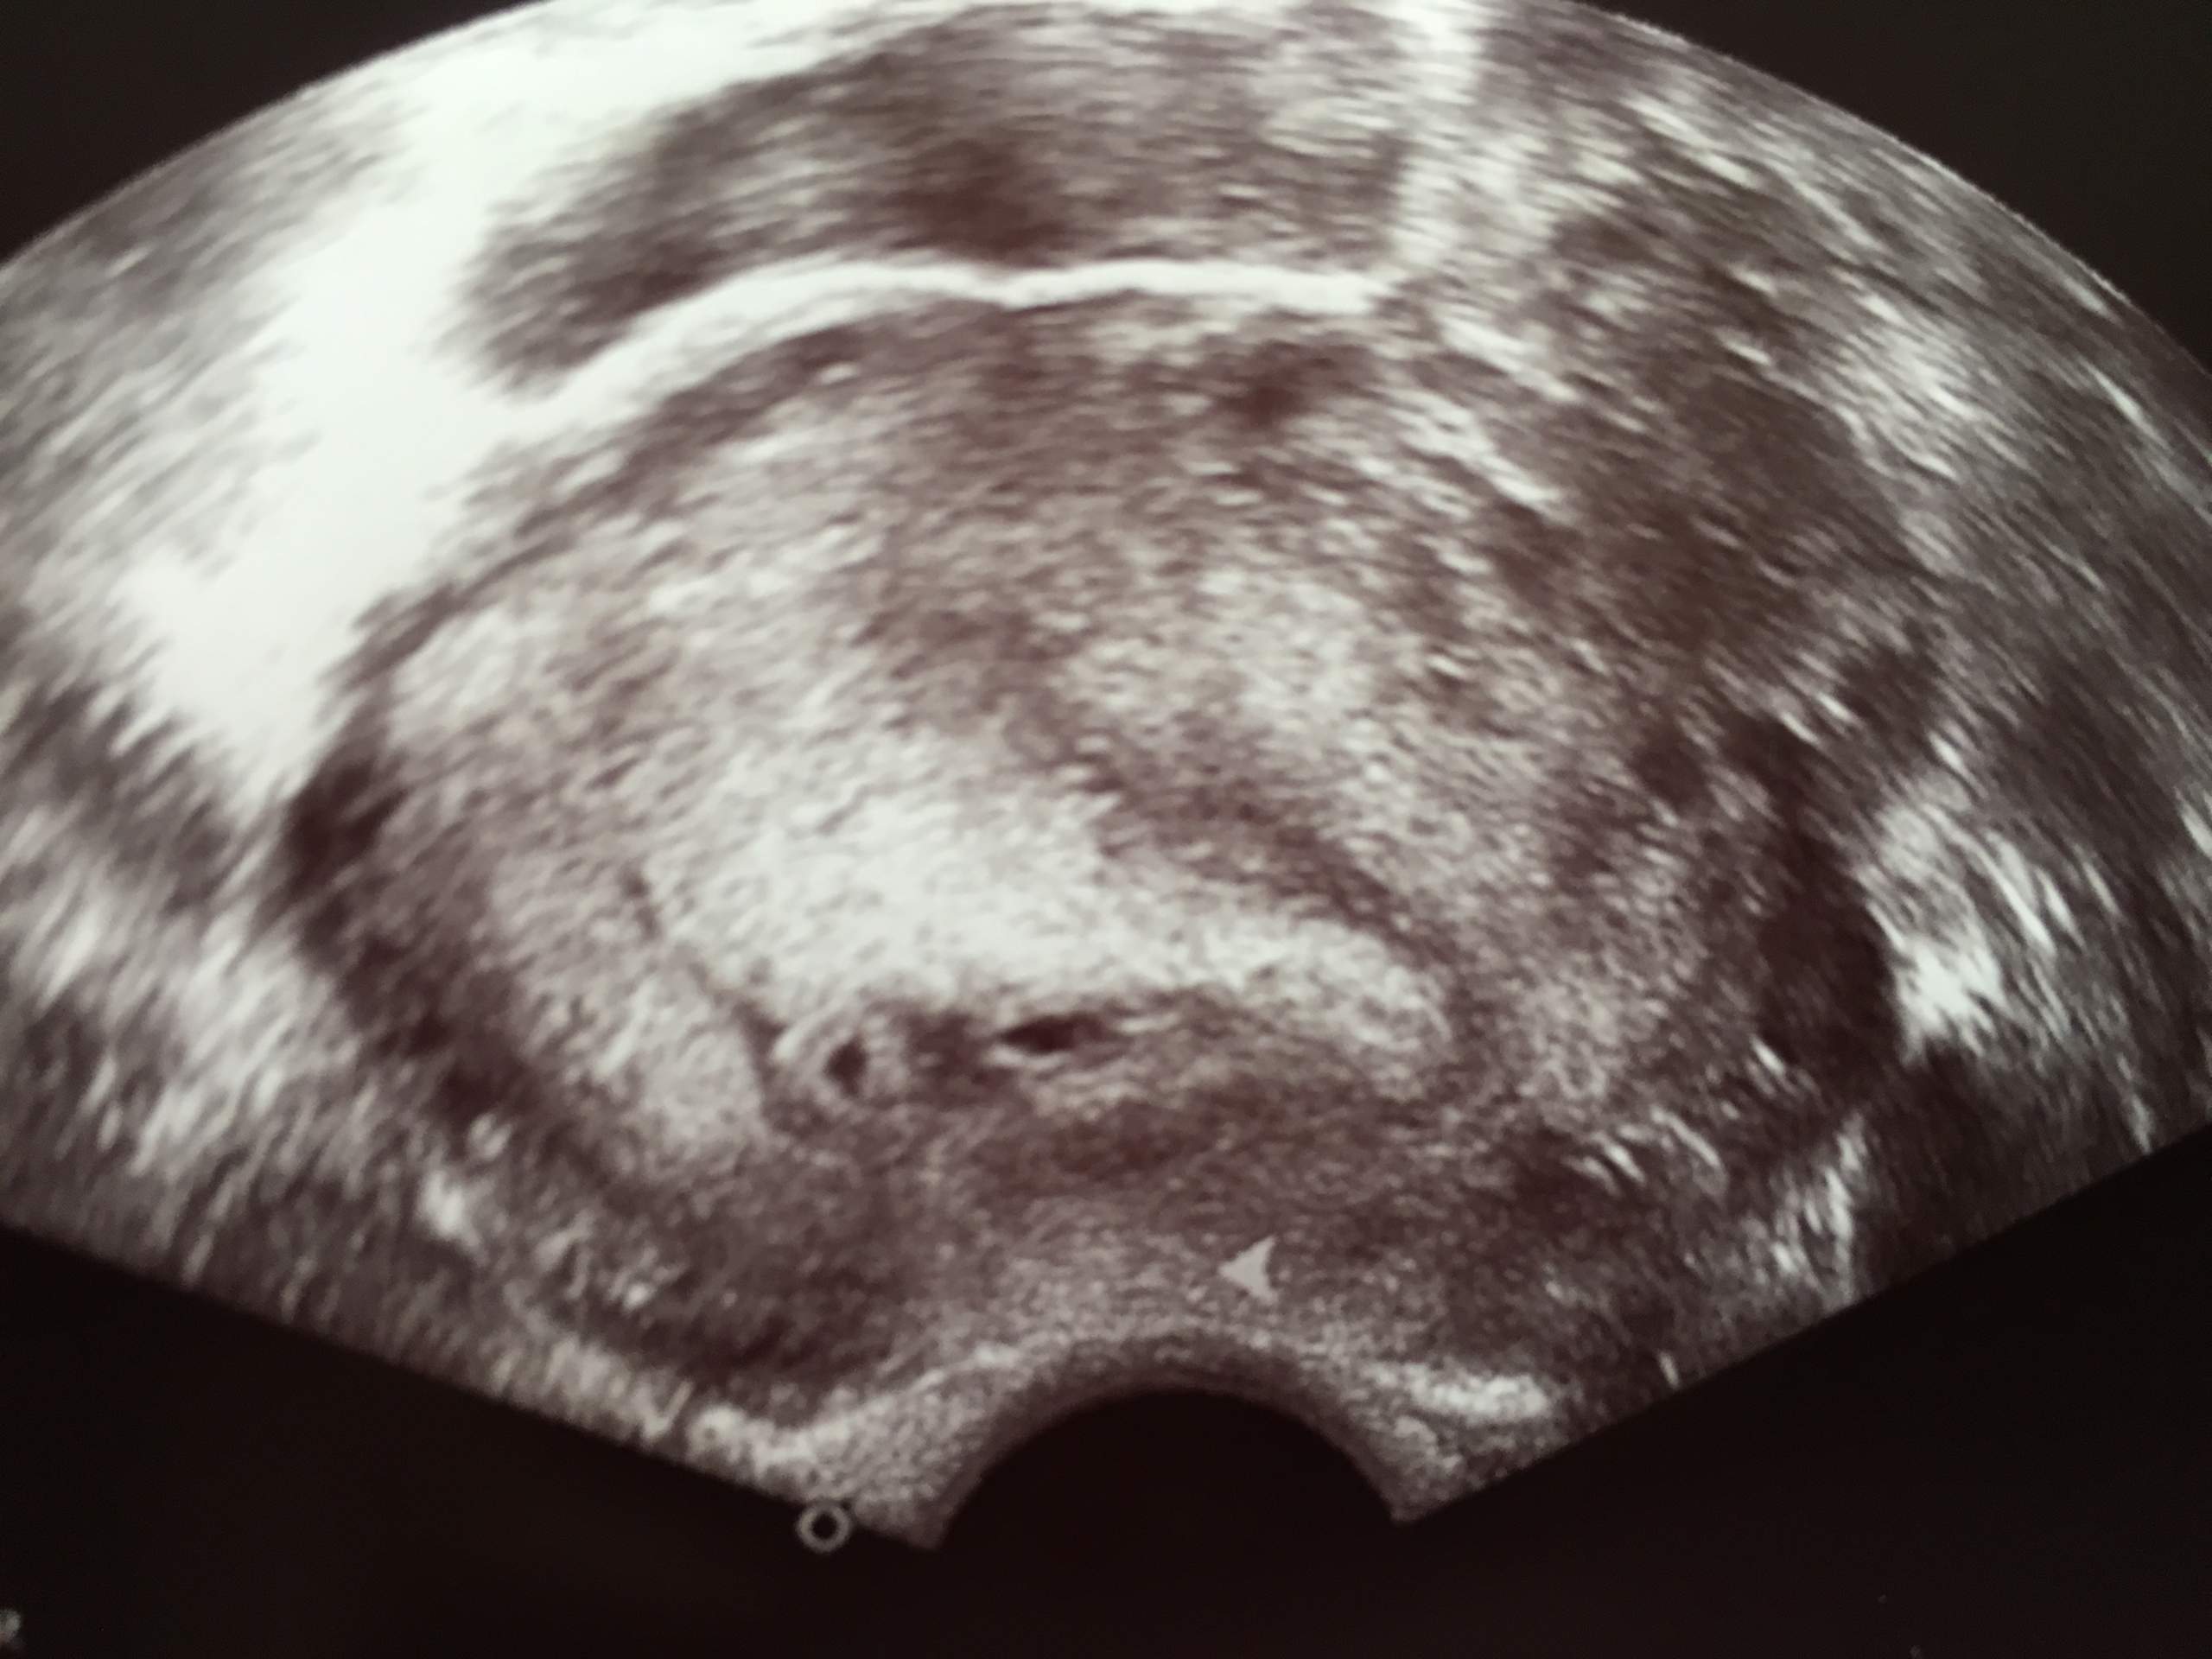

Das hat auch mein Frauenarzt so berechnet. SSW im Ultraschall stimmt nicht mit tatsächlicher SSW überein. Bei mir konnte man bei 53 eindeutig zwei gleich große Fruchthöhlen mit Inhalt erkennen.

Schwangerschaftswoche Zwillinge in SSW 5. 5 2 ssw ultraschall zwillinge. In der Regel werden Zwillinge bereits bei der ersten Ultraschalluntersuchung entdeckt die etwa in der sechsten Schwangerschaftswoche erfolgt.

Zu den sichersten Anzeichen dass Du Zwillinge erwartest gehören zwei Herzschläge im Ultraschall.

SSW im Ultraschall stimmt nicht mit tatsächlicher SSW überein. Woche SSW5 Alter 3 Wochen. Ihre Zwillinge in der 6. Zu den sichersten Anzeichen dass Du Zwillinge erwartest gehören zwei Herzschläge im Ultraschall. Demnach wäre ich jetzt 52 also 6. Sie sind 5 Wochen schwanger SSW 5 oder in der 6. Unsere zwillinge beim 3D Ultraschall in der 27. Links noch der Querschnitt des Abdomens mit angeschnittener Magenblase. Januar 2012 um 2004.